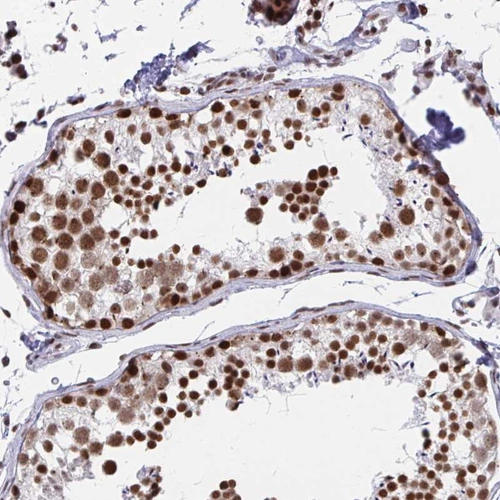

Immunohistochemistry analysis in human testis and skeletal muscle tissues using HPA059621 antibody. Corresponding YTHDF2 RNA-seq data are presented for the same tissues.